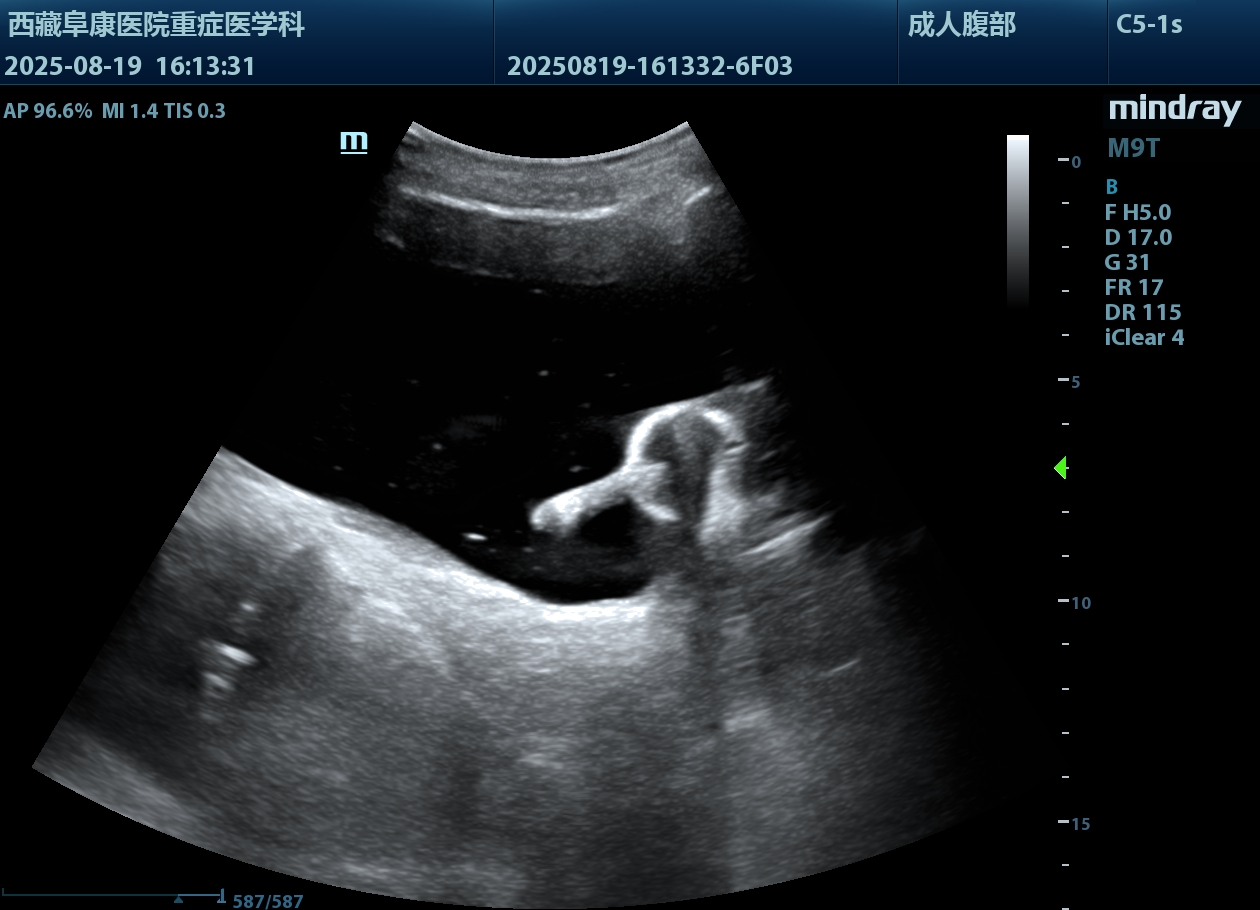

由于情況緊急,醫護人員沒有半分遲疑,除了導尿所需的物品,考慮到老人年紀大了,必須先確認情況,半點馬虎不得,他們特意帶上B超機,拎起出診箱,火速趕往老人家中。

推開門,只見老人蜷縮在藏式床上,身子微微發顫。醫護人員放輕腳步,俯身輕聲安撫:“大爺,我們先幫您看看情況,不難受的。”先是輕柔查體,感知膨隆小腹下的膀胱充盈度;再用B超機細致探查,醫護人員邊操作邊低聲講解流程。慢慢地老人緊繃的身體放松下來,默許了檢查。可是提到導尿時,還是擺著手抗拒。醫護人員和家屬耐著性子反復勸說,許久后,他終于輕輕點了頭。